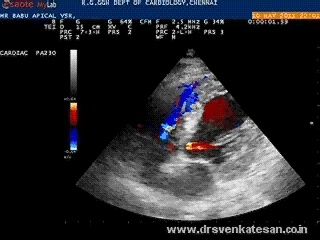

Mechanical complications are not rare  following acute MI .In fact , it closely competes with electrical deaths . Many times it is not recognised  and get wrongly labeled as  simple pump  failure .

Echocardiography has revolutionised the way , we approach these deadly complication.(Of course , many  deaths  could  not be prevented still !)

The rupture site is predetermined by the patients fate !. If the tear occur in free wall of LV  , in all likely-hood ,we are going to lose the patient. If he is blessed  , the rupture take place in the interventricular  septum .Here , the issue is less disastrous as the  blood is  simply shunted to a different chamber .In fact , some consider VSR puts an ailing ventricle at  a slight hemodynamic advantage which is referred to as decompression .   The LVEDP has  a biphasic response to VSR  .An  initial raise bfollowed by a flat response.This has a clinical correlation too  with a temporary deterioration and subsequent stabilisation.

An irregular tear in the mid ventricular septum

This patient did well with initial medical support and referred for surgery electively

• The doppler  VSR jet if  reaches 4-5 m/sec (65-100 mmhg) the prognosis is often good , as it indirectly  reflects the native LV function .A ventricle which could generate 100mmhg pressure head,  even after a supposedly large MI  is great by any standards.These are the ventricles  that fight till the end and patients do well in the  adverse circumstances.

• In the  other end of the spectrum we have a VSR with a faint murmur and 3m/sec jet .They will be  hypotensive and end up in shock soon.